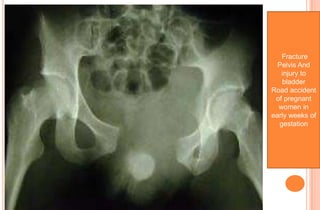

Fracture

Pelvis And

injury to

bladder

Road accident

of pregnant

women in

early weeks of

gestation

Fracture Pelvis And injury to bladder Roadaccident of pregnant women in early weeks of gestation